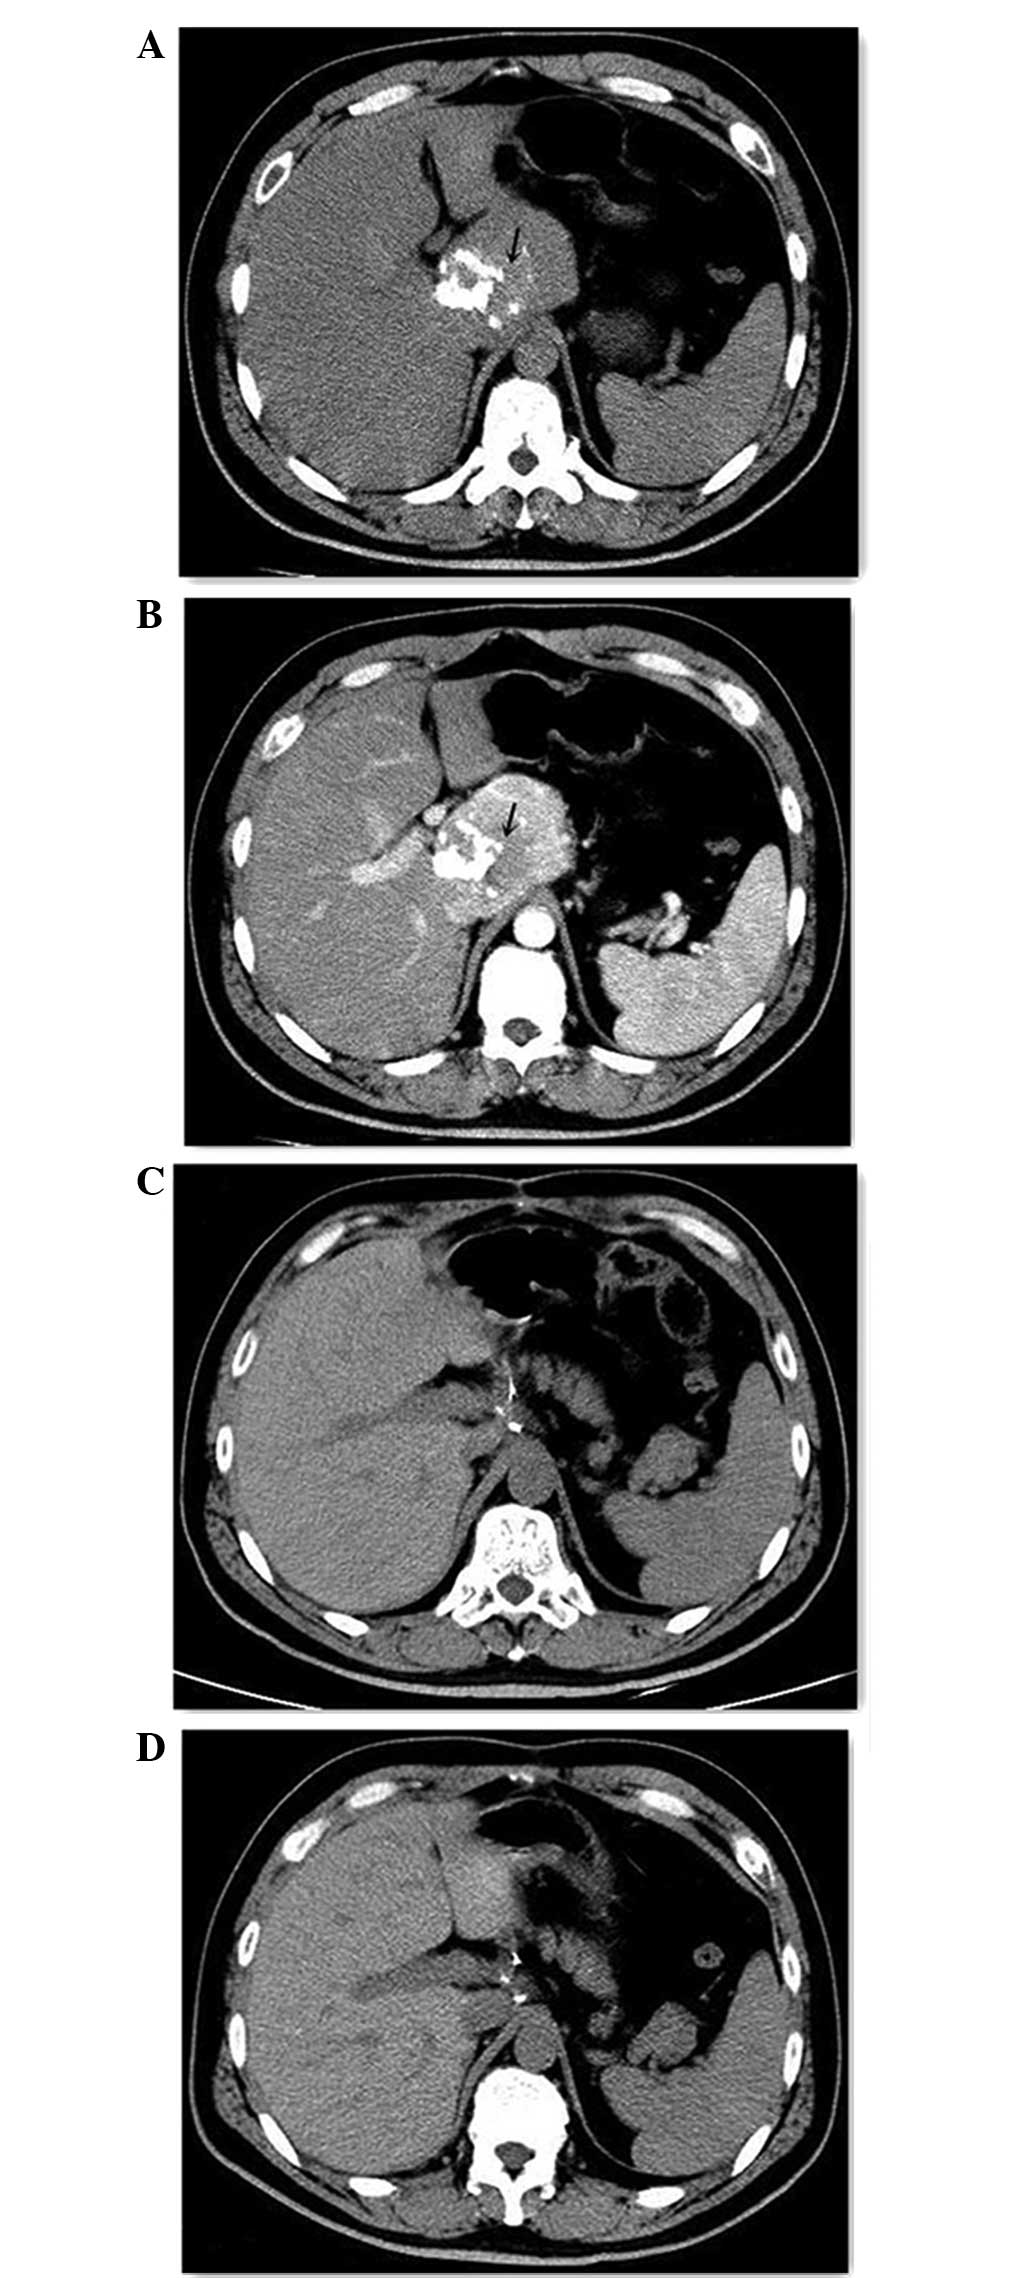

An abdominal ultrasound (MyLab™Twice; Esaote Europe BV, Cambridge, UK) revealed a 67×55-mm hypoechoic mass in the region between the first liver segment and the pancreas, which possessed calcification on the inside. The abdominal contrast-enhanced CT scan (Brilliance iCT; Philips Healthcare, Andover, MA, USA) reveled a 70×72-mm mass on the border of the caudate lobe. The non-enhanced phase revealed patchy calcification inside the mass (Fig. 1A), and evident contrast enhancement was observed in the mass during the arterial phase (Fig. 1B). The CT scan also revealed possible infiltration into the head and neck of the pancreas, indicating a solid pseudopapillary tumor of the pancreas.

Figure 1.

Pre-operative and post-operative computed tomography showing the retroperitoneal tumor (arrow) in the (A) non-enhanced phase, (B) the arterial phase, (C) at 1 month post-surgery and (D) at 5 months post-surgery.

Immunohistochemistry for the biomarkers was performed manually. Briefly, antigen retrieval was performed using citrate buffer (pH 6.0; Sangon Biotech Co., Ltd., Shanghai, China). Sections were subsequently incubated with the following antibodies: Mouse monoclonal anti-human cluster of differentiation 20 (clone 7D1; dilution, 1:200; catalog no., NCL-CD20-7D1; Leica Biosystems), mouse monoclonal anti-human cluster of differentiation 3 (clone LN10; dilution, 1:100; catalog no., NCL-L-CD3-565; Leica Biosystems), mouse monoclonal anti-human cluster of differentiation 21 (clone 2G9; dilution, 1:60; catalog no., NCL-CD21-2G9; Leica Biosystems) and rabbit anti-human immunoglobulin G cluster of differentiation 23 (clone RM104; dilution, 1:100; catalog no., RM-9123-S0; Thermo Fisher Scientific, Inc.), in a humidified chamber for 1 h at 37°C. Sections were then incubated with horseradish peroxidase-conjugated goat anti-mouse secondary antibody (part of the EnVision+ System-HRP kit; ready to use; catalog no., K4007; Dako, Glostrup, Denmark). Following incubation, 3,3′-diaminobenzidine (part of the EnVision+ System-HRP kit) was applied for ~2 min. Slides were subsequently stained with hematoxylin (Sangon Biotech Co., Ltd., Shanghai, China). A negative control was designed by using phosphate-buffered saline (Sangon Biotech Co., Ltd., Shanghai, China) rather than primary antibody. The immunohistochemical analysis revealed the expression of cluster of differentiation 3, 20, 21 and 23 subsequent to staining. Due to these findings, the patient was diagnosed with CD of the hyaline vascular type. The patient was followed up and is currently free of disease 20 months subsequent to resection (Fig. 1C and D).